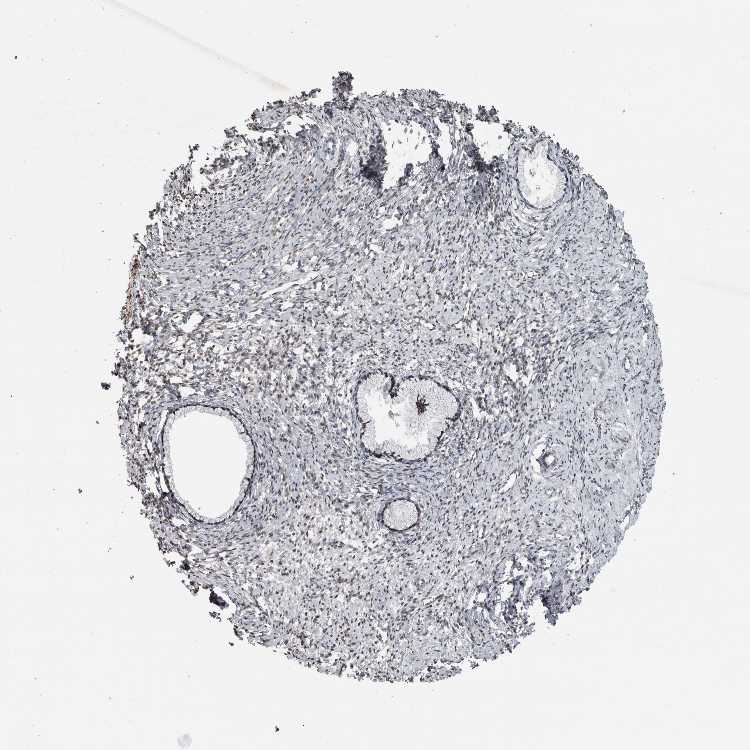

TISSUE PRIMARY DATA CERVIX Show tissue menu

Cervix

CERVIX - Antibody stainingi

Antibody staining in the annotated cell types in the current human tissue is reported as not detected, low, medium, or high, based on conventional immunohistochemistry profiling in selected tissues. This score is based on the combination of the staining intensity and fraction of stained cells.

Each image is clickable and will lead to virtual microscopy that enables deeper exploration of all samples and also displays staining intensity scores, fraction scores and subcellular localization as well as patient and tissue information for each sample.

Antibody HPA023447Antibody HPA023571Antibody HPA025941

Glandular cells MediumHighHigh

Squamous epithelial cells --High